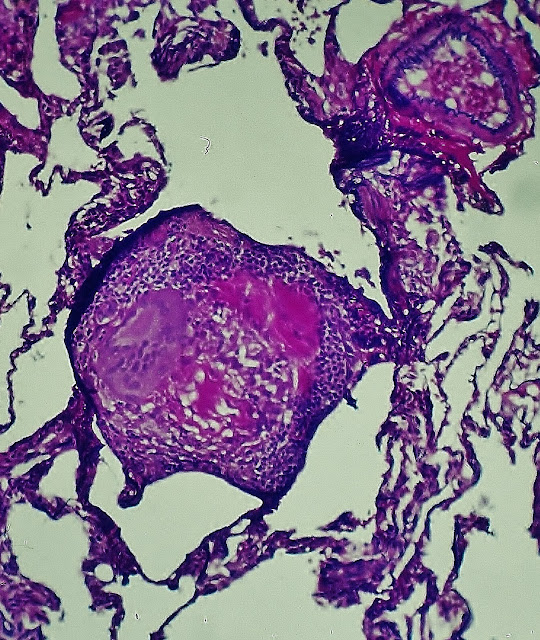

Fig.7.-Two granulomas, one of which contains hyaline material in the center. Hematoxylin-eosin-phloxine. Prof.Garfia.A

Fig.8 .- The first granuloma in which it was observed the presence of multinucleated giant cells and a lymphocytic corona. Hematoxylin-eosin-elastic.

Fig 9.-Granuloma "soft", consisting of eosinophilic material remains, the presence of multinucleated giant cells and epithelioid cells. Prof.Garfia

Fig.10 .- Granuloma adjacent to the wall of a bronchiole, material containing amorphous eosinophilic center. Its location is suggestive of hydatid cyst bronchogenic dissemination. In certain cases has raised the differential diagnosis of granulomatosis bronchocentric (bronchocentric granulomatosis). Prof.Garfia.A

Fig.11.-up to the same cut-metenamina.Prof.Garfia.A silver stained

Fig.12.-Granuloma in the center containing eosinophilic material, suggesting amorphous, with the photograph, the presence of a parásito.Prof.Garfia.A

Fig.13 .- methenamine silver, the same court distinguished the present material, red brick, shaped brackets, very suggestive hydatid cyst, surrounding a mass of amorphous material in the center of granuloma.Prof.Garfia.A

Fig.16 .- Granuloma containing membrane remnants of germinative membrane laminated inactiva.Prof.Garfia.A

Fig. 17 .- This was the first granuloma which could note that had remnants of laminated membrane and membrane germination inactiva.Prof.Garfia.A

Fig.18 .- Granuloma stained with Masson trichrome, presented remnants of the laminated membrane and central necrotic areas containing necrotic vesicles. Prof.Garfia.A

Fig.19.-Detail anterior.Prof.Garfia.A

Fig.20.-Review polarized light of a granuloma containing four quistes.Prof.Garfia.A

Fig.21 .- Pulmón.Plata-methenamine. The photograph shows four cysts encompassed by the same cover of dense collagen fibers orientado.En the center of each granuloma lamellar fragments are distinguished. Prof.Garfia.A

Fig.22.-Pulmón.Plata-methenamine. Granuloma containing small inactive hydatid cyst. Prof.Garfia.A

Fig.23 .- Detail of the previous figure showing the cover laminated and germinative membrane or prolígera, detached from aquella.Plata-methenamine. Prof.Garfia.A

Fig.24 .- Large increase showing the morphology of the granuloma in which you can see, clearly, the laminated structure of the cuticle or outer layer of the cyst wall and detachment of the germinative layer of the cyst into the light "inactive." Silver-methenamine . Prof.Garfia.A